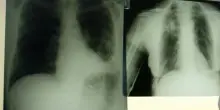

Roma, 1 ago. (Adnkronos Salute) – Portare innovazione terapeutica per i pazienti con carcinoma polmonare a piccole cellule (Sclc), una delle forme più complesse di tumore al polmone. E’ l’impegno che PharmaMar rinnova in occasione della Giornata mondiale del tumore al polmone, che si celebra oggi, 1 agosto, con il suo approccio “unico e innovativo” […] L'articolo Giornata mondiale del tumore al polmone, PharmaMar: “Dal mare nuove armi per vincerlo” proviene da La Ragione.